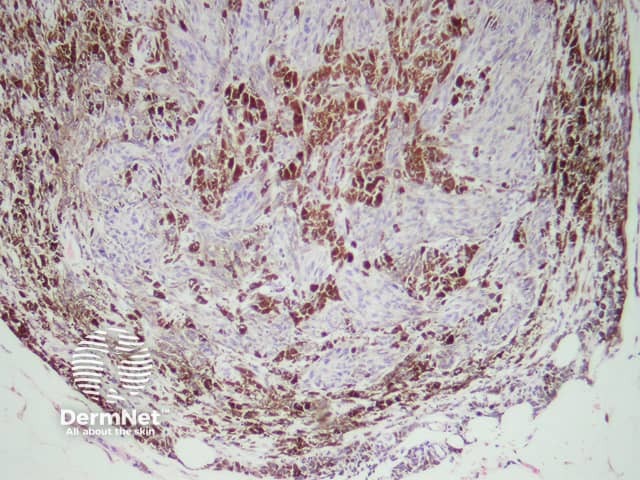

If there is any uncertainty about the diagnosis, an excisional biopsy may be performed. The histopathology of blue naevus reveals spindle-shaped melanocytes in the mid-dermis, made of epithelioid cells with heavily pigmented cytoplasm. SOX10 and Melan-A stains are positive.

Histopathology of dermal dendritic melanocytes that make up a common blue naevus

Histopathology of a cellular blue naevus - cells may be round oval or fusiform